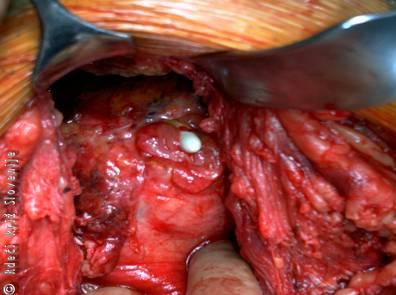

Slika 4

Medoperativna slika raztrganja sečnega mehurja (iz mehurja štrli vrh urinskega katetra).